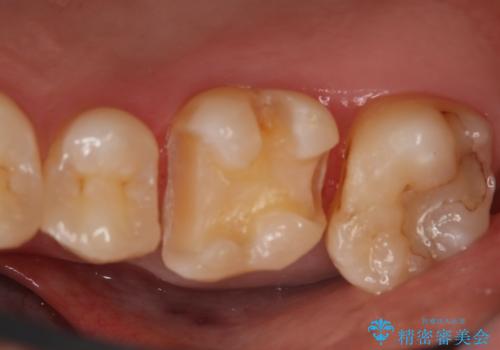

- 右上6番の銀歯をセラミックに変えたいと希望された患者様です。

切削量、形態を考慮し、セラミックインレーでの治療を計画しました。

銀歯と虫歯を除去した上でCRで裏層し形態を整えて印象を行っています。